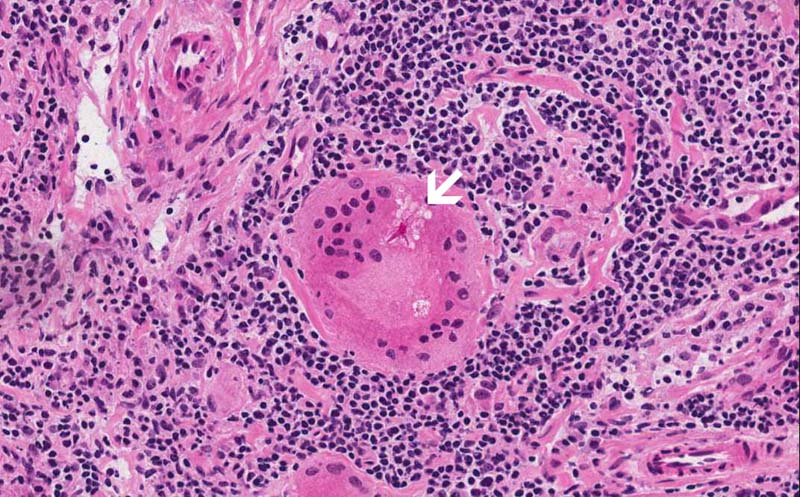

Area 2: Asteroid bodies (arrow) can be seen in this giant cell.

• Granulomas are roughly round to oval to irregular collections of histiocytes often with mutinucleated giant cells. They can be seen in multiple types of disease processes that include sarcoidosis, fungal infection, mycobacterial infections, berylliosis, foreign body, granulomatous changes of neoplasms particularly lymphomas and germ cell tumors, Wegerner's granulomatosis, and other conditions.Granulomatosis in sarcoidosis is usually non-necrotizing but necrosis may occur. Inclusions such as Asteroid bodies (Area 2) and Schaumann bodies can be seen in sarcoidosis. These inclusions are suggestive, however, non-diagnostic for sarcoidosis.